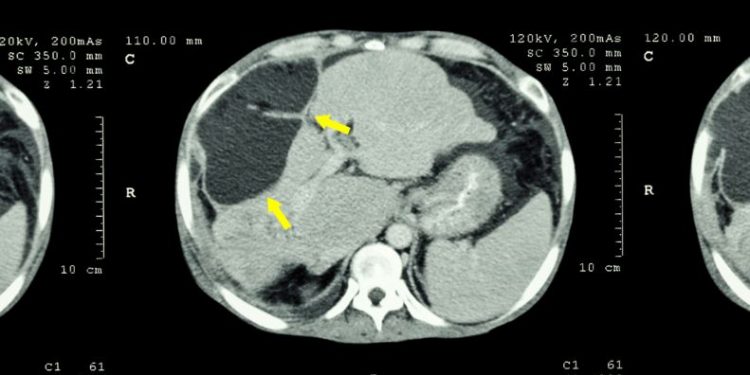

Symptoms of stage 4 liver cancer are similar to those associated with advanced chronic liver disease, including abdominal pain and discomfort, fatigue, weight loss, jaundice (yellowing of the skin or whites of the eyes), loss of appetite, and diarrhea. In some cases, a person may develop ascites, fluid accumulation in the abdomen, or encephalopathy, changes in mental status, or severe watery diarrhea. Often, doctors find this type of cancer through regular physical exams and blood tests that check for liver function, bile flow, and alpha-fetoprotein, which is a tumor marker commonly found in patients with this disease.